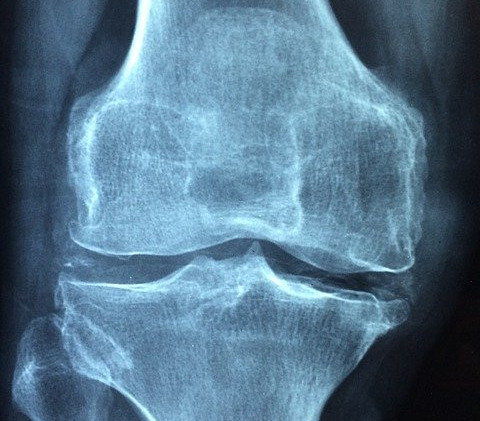

The one treatment that seems to work well is in a case where the patient is getting pain from a disease called osteoarthritis of the knee.

Osteoarthritis is characterized by the bone getting loose and becoming more vulnerable, causing an increase in pain.

How Is Red Light Therapy Used to Help With Degenerative of the Knee?

Although degenerative arthritis of the knee is a fairly common and serious condition, the best way to know how is red light therapy used to help with this disease?

In many cases, there is very little that you can do to treat this condition but if you find a good course of treatment, you will be able to slow down the progression of the disease and possibly even stop it altogether.

The main symptom of degenerative arthritis of the knee is pain in the joints.

This pain can be excruciating.

Other symptoms include stiffness, which can interfere with daily activities.

The American College of Rheumatology has noted that red light therapy has been beneficial for a variety of ailments.

https://www.ncbi.nlm.nih.gov/pubmed/1727843

Stelian J1, Gil I, Habot B, Rosenthal M, Abramovici I, Kutok N, Khahil A

Geriatric Medical Center, Shmuel Harofe Hospital, Beer Yaakov, Israel.

This condition is just one of them.

It is possible that red light therapy can be used to help control symptoms like arthritis.